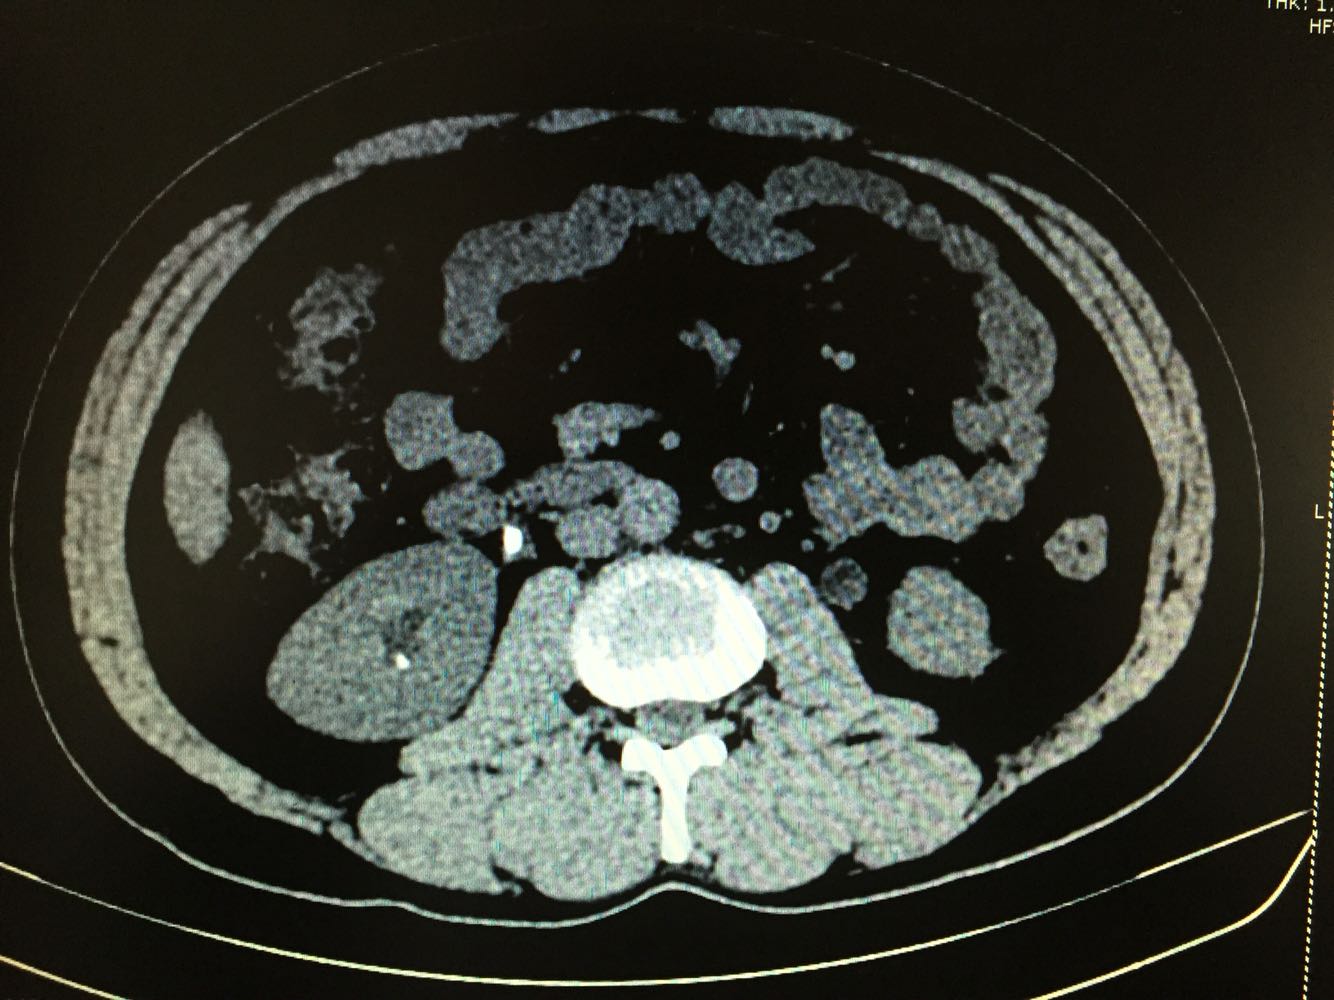

双侧输尿管结石

体检发现双侧输尿管结石,双肾积水1周,尿量无明显变化

双侧输尿管结石,双肾积水

治疗方案,拟先行左侧输尿管镜下碎石,再行右侧输尿管软镜下碎石术。